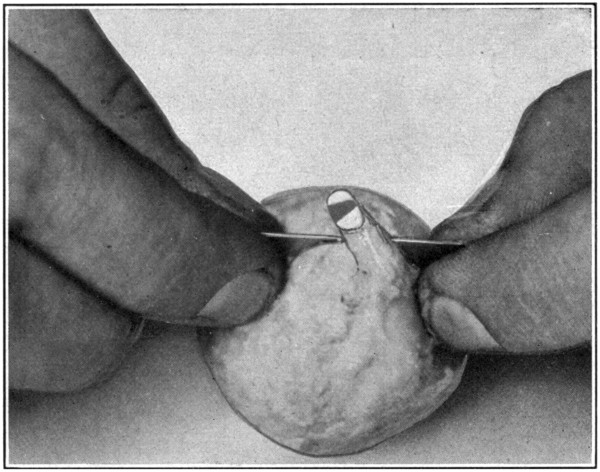

By practising on an enucleated eye, one may gain considerable ability in the use of the ophthalmoscope, and also learn to recognize the blood-vessels and other important parts of the retina. To do this, the eye to be examined must be very fresh, for only in this condition will the cornea and lens be sufficiently clear to permit rays of light to enter the inside of the eye.

However, since the pupil is oblong in shape, and often only a narrow slit—but several millimetres in diameter—the field presented for observation is a rather limited one. To increase the pupillary aperture, take a pin, and force the point through the cornea about three or four millimetres from the corneo-scleral junction, and at right angles to the direction of the parallel edges of the pupil. After the pin has been pushed through until it has reached to within a short distance (one[107] millimetre) of the edge of the iris, carefully pick up the iris by raising the pin into a position perpendicular to the cornea, and force the pin further down into the eye. The pupil will have been enlarged on one side. Do the same thing on the opposite side, and at each extremity of the pupil. (Fig. 55.)

Fig. 55—Showing one pin before the iris has been picked up and pulled back, and three pins after the iris has been picked up and pulled back.

[108]

Fig. 56—Showing method of gathering up the extrinsic tissues in order to get rid of the pucker in the cornea.

The pupil will now have been made square, and so large that no difficulty will be experienced in reflecting either light into the eye, or[109] in examining the inside of the eye. Care must be taken not to lacerate the anterior surface of the lens when the iris is drawn back by the pins.

Putting the pins into the cornea, and using them as levers with the point of entrance in the cornea as a fulcrum, will pucker the cornea considerably, and a good clear fundus cannot be obtained. This is easily overcome. Simply gather up all the tissues surrounding the eye, force them backward, and hold them firmly with the fingers of the left hand. (Fig. 56.) The right hand is then free to handle the skiascope or ophthalmoscope, so that the interior of the eye may be thoroughly examined.